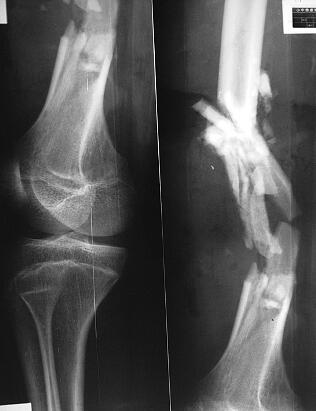

患者,男,19岁。因“撞伤右股骨骨折术后窦道流脓4个月余”于2002年6月4日入院。于2002年1月28日骑摩托车时撞伤右大腿,当时局部肿痛较重,畸形,大腿前侧有一3cm挫裂口,其内可见游离的骨折块,活动受限,遂至当地县骨科医院就诊,拍摄X线片(图1),诊断为右侧股骨开放性骨折,行清创、切开复位支架固定术(图2),术后2周时伤口处红肿,向外流脓;细菌培养为肺炎克雷伯菌生长,给予二次清创、持续冲洗引流,使用抗生素6周后,切口愈合,血常规正常,常规出院。骨折固定术后2个月时,局部再次红肿,发热,跳痛,切口旁出现2个窦道,有脓性物外溢,细菌培养为耐药性金黄葡萄球菌、肺炎克雷伯菌生长,再次住院,静输敏感抗生素4周,窦道间断性流脓,间有碎骨片溢出。现因右大腿窦道流脓量大,故而转诊我院。

图1 伤时X线片